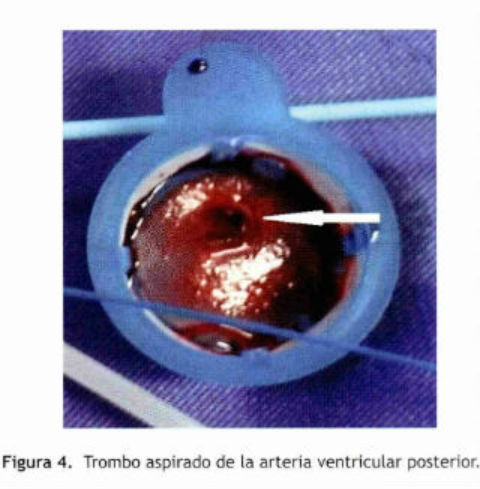

Se realizó una trombo aspiración durante el procedimiento con la restauración del flujo coronario TIMI 3 sin presencia de lesiones ateromatosas significativas. Los constituyentes principales del trombo que se producen en las venas y las cámaras cardiacas son los glóbulos rojos y fibrina, por lo tanto su apariencia macroscópica es roja.

Debido a estos hallazgos en el material aspirado (Figura 4) que mostró la acumulación de glóbulos rojos y fibrina podemos conjeturar que el IMA fue causado por embolismo coronario complicando la FA.